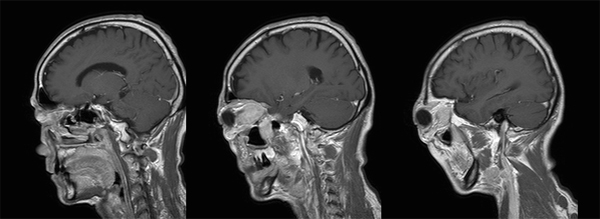

診断:下垂体炎、硬膜炎、三叉神経の炎症性偽腫瘍

【画像所見】

T1強調画像

造影後矢状断:

IgG4 計ってもらうと上昇あり

下垂体炎、硬膜炎、三叉神経の炎症性偽腫瘍